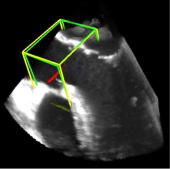

利用2891次心脏超声检查的数据集,Ghesu等结合深度学习和边缘空间学习进行医学图像检测和分割[12]。“大参数空间的有效探索”和在深度网络中实施稀疏性的方法相结合,提高了计算效率,并且与同一组发布的参考方法相比,平均分割误差减少了13.5%,八位患者的检测结果如图4所示。Brosch等人利用MRI图像上研究多发性硬化脑病变分割的问题。开发了一种3D深度卷积编码器网络,它结合了卷积和反卷积[13],图5.增加网络深度对病变的分割性能的影响。卷积网络学习了更高级别的特征,并且反卷积网络预进行像素级别分割。将网络应用于两个公开的数据集和一个临床试验数据集,与5种公开方法进行了比较,展现了最好的方法。Pereira等人的研究中对MRI上的脑肿瘤分割进行了研究,使用更深层的架构,数据归一化和数据增强技巧[14]。将不同的CNN架构用于肿瘤,该方法分别对疑似肿瘤的图像增强和核心区域进行分割。在2013年的公共挑战数据集上获得了最高成绩。

图4示例图像显示了不同患者的检测结果从测试集。检测到的边界框以绿色显示,标准的框以黄色显示。原点位于每个框中心的线段定义相应的坐标系